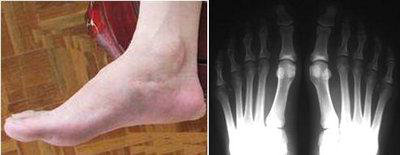

(图:张先生的脚关节已经开始变形,有明显浮肿)

经过详细的检查显示,化验:血尿酸:720 μmol/L,ALT:54,AST:43,肌酐值(肾功):71(59-104),抗“0” 定量检测(ASO):201.8。X线示:右足跖骨骨头处出现溶骨性缺损。根据检查结果,我院医生杜爱华为他制定了详细的治疗计划。

(图:三个疗程的治疗,张先生的脚步已恢复正常,浮肿消失)